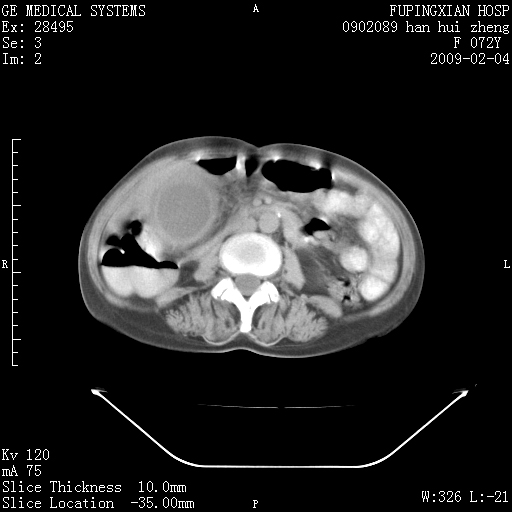

标题: CT17930:F72Y,右腹部包块5日,脐右扪及一包块,触痛。 [打印本页]

标题: CT17930:F72Y,右腹部包块5日,脐右扪及一包块,触痛。

胆囊增大,虽然内壁光滑,但囊壁不均匀性增厚,胆囊窝积液,所以首先考虑胆囊炎,但并不能排除胆囊癌的可能。诊断胆囊癌的依据是:胆囊壁呈不均匀性明显增厚,部分层面胆囊与肝脏界限不清。